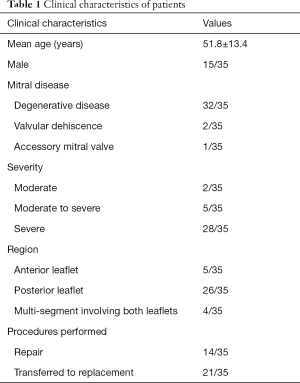

From September 2016 to November 2018, we retrospectively enrolled 35 patients who had MR and were prepared to have MVR at Renmin Hospital of Wuhan University (15 male patients, 20 female patients). The inclusion criteria were the following: moderate or more severe MR; anatomy of the MV suitable for MVR (Carpentier type II, part of Carpentier type I with clefts or isolated damage to the valve from previous infective endocarditis); good 3D-TEE image quality that clearly displayed the mitral leaflets; no history of allergy to CT contrast agents. Of note, for patients with mitral annular calcification, the severity of the calcification was qualitatively determined as mild (limited increased echodensity of aortic annulus), moderate (extensive echodensity involving >50% of ring circumference, but with preservation of leaflet mobility), and severe (extensive echodensity involving entire circumference of aortic ring, and with limitation of leaflet excursion) (13). The exclusion criteria were the following: severe cardiac dysfunction [left ventricular (LV) ejection fraction (EF) <30%]; severe renal dysfunction; severe calcification of the annulus; severe calcification and fibrosis of the MV leaflets. We excluded the patients with an EF <30% according to the 2017 American College of Cardiology/American Heart Association (AHA/ACC) Focused Update of the 2014 AHA/ACC Guideline for the Management of Patients with Valvular Heart Disease (14), which indicates that patients with an EF <30% are weakly recommended (Class: IIb) for MV surgery. The study was conducted in accordance with the Declaration of Helsinki (as revised in 2013). The study was approved by Clinical Research Ethics Committee of Renmin Hospital of Wuhan University (No. WDRY2018-K032) and informed consent was taken from all individual.

The 35 patients included in our study (Table 1) comprised 2 patients with moderate MR, 5 patients with moderate-to-severe MR and 28 patients with severe MR. Of them, 32 patients suffered from MV prolapse attributed to degenerative disease, including 26 cases of posterior MV leaflet (PML) prolapse, 2 cases of AML prolapse and 4 cases of multi-segment prolapse involving both the AML and PML. In total there were 14 cases of successful MVR and 21 cases of transfer to MV replacement.

In all patients, the grade of MR and the VCW measured in vitro and in vivo before surgery were highly consistent (Tables 2,3, Figure 6). With the 3DP model, 3 patients were assessed as moderate MR, 4 as moderate-to-severe MR, and 28 with severe MR. Only one patient was assessed as moderate MR in vitro but had moderate-to-severe MR in vivo, and one patient was assessed as moderate-to-severe by CFD but was severe in vivo (Table 2).